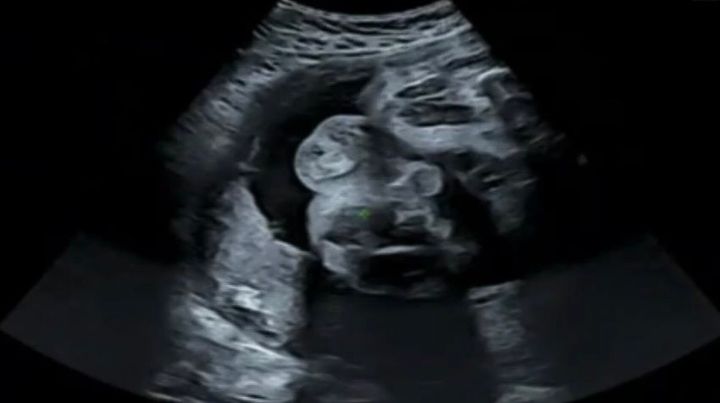

妊婦検診で撮影するエコー写真は、まだ顔などがはっきり写っていないことも多いですよね。そのため、見る角度や想像によっては、別の何かが写っているように見えることもあります。

昨日の妊婦健診のエコーお母さんに見せたら「お腹の中でスヌーピー飼っとる?」って言われて気づいた瞬間超笑った

この写真を見て、「たしかにスヌーピーに見える!」と思った方も多いのではないでしょうか。

一度そう見えてしまうと、もうスヌーピー以外には見えなくなるほどですよね。